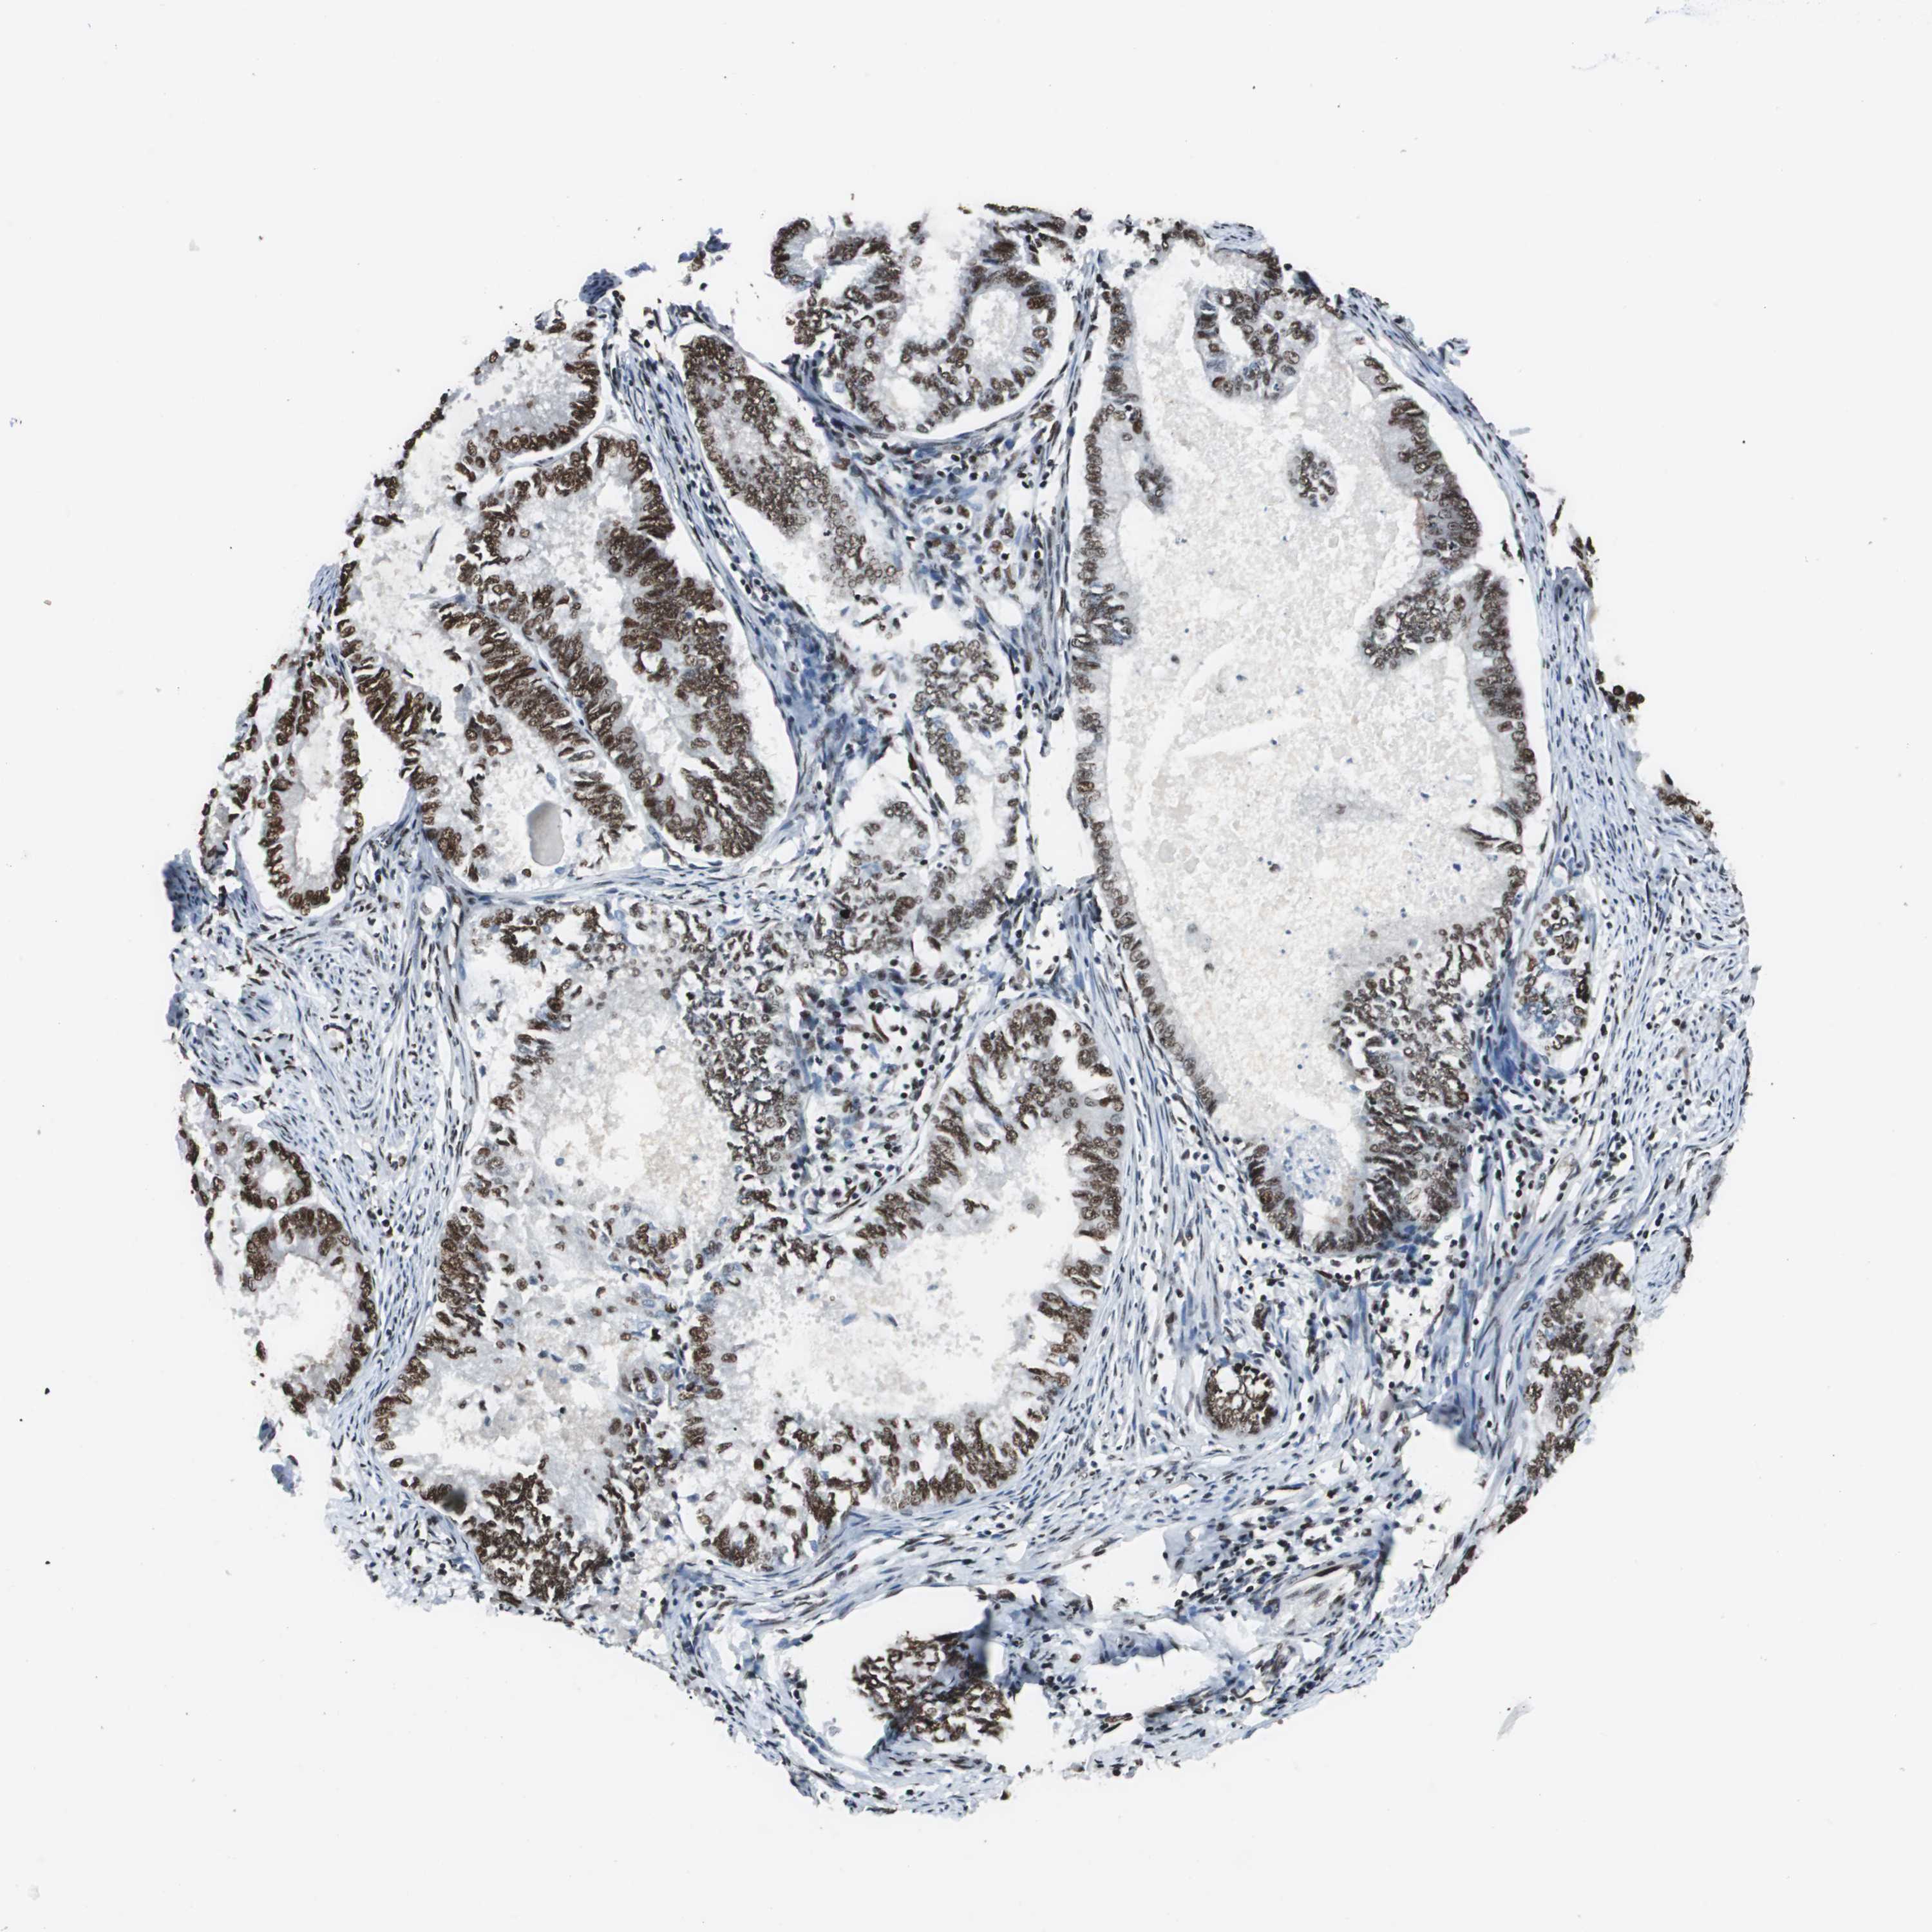

ENDOMETRIAL CANCER - Protein expressioni

A mouse-over function shows sample information and annotation data. Click on an image to view it in a full screen mode. Samples can be filtered based on level of antibody staining by selecting one or several of the following categories: high, medium, low and not detected. The assay and annotation is described here.

Note that samples used for immunohistochemistry by the Human Protein Atlas do not correspond to samples in the TCGA dataset.

Antibody stainingi

Antibody staining in the annotated cell types in the current human tissue is reported as not detected, low, medium, or high, based on conventional immunohistochemistry profiling in selected tissues. This score is based on the combination of the staining intensity and fraction of stained cells.

Each image is clickable and will lead to virtual microscopy that enables deeper exploration of all samples and also displays staining intensity scores, fraction scores and subcellular localization as well as patient and tissue information for each sample.

Antibody HPA006982

Staining

High

Medium

Low

Not detected

Intensity

Strong

Moderate

Weak

Negative

Quantity

>75%

75%-25%

<25%

None

Location

Nuclear

Cytoplasmic/membranous

Cytoplasmic/membranous,nuclear

Adenocarcinoma, NOS